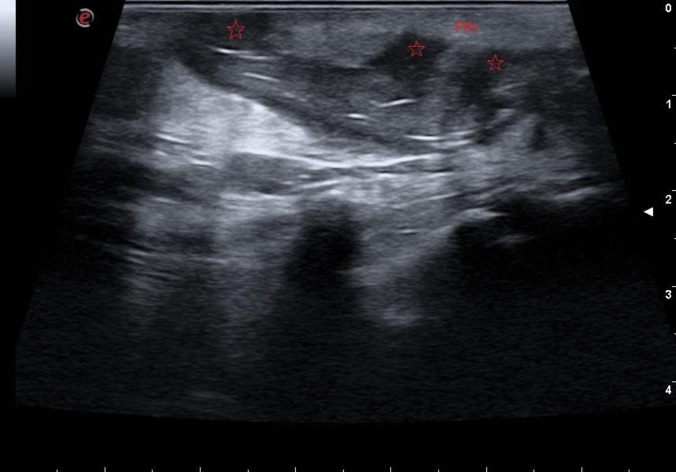

Background: Pilonidal disease (PD) is frequently associated with high recurrence rates and delayed healing, particularly in complex or recurrent cases. While Endoscopic Pilonidal Sinus Treatment (EPSiT) has improved postoperative recovery and patient satisfaction, its effectiveness can be limited by incomplete identification of fistulous tracts. Intraoperative ultrasound (IUS) offers real-time visualization of subcutaneous structures and may aid in detecting hidden tracts during surgery. This study evaluates the clinical outcomes of combining IUS with EPSiT in the treatment of complex and recurrent PD.

Materials and methods: A retrospective cohort, single-center study was conducted on patients with recurrent and complex PD treated between 2018 and 2021 using IUS in conjunction with EPSiT. All patients had a minimum follow-up of 36 months. The study recorded the number of cases in which IUS identified additional fistulous tracts and led to a modification of the surgical strategy, as well as clinical outcomes including recurrence rate, time to wound healing, and incidence of incomplete wound healing.

Results: Nineteen patients were included (14 males, 73.7%; mean age of 35.4 ± 6.4 years). The mean operative time was 42 min, with IUS requiring an additional 6 min. IUS identified previously undetected fistulous tracts in 6 patients (31.5%), leading to modifications in the surgical strategy. At 36-month follow-up, disease persistence (recurrence or incomplete healing) was observed in 5 patients (26.3%). Recurrent cases were successfully managed with additional procedures, achieving 100% healing after reintervention.

Conclusions: Intraoperative IUS identified previously undetected secondary tracts in 31.5% of patients, leading to a modification of the surgical approach. Further comparative studies are needed to validate its effectiveness and assess its potential role as a standard adjunct in the surgical management of pilonidal disease.